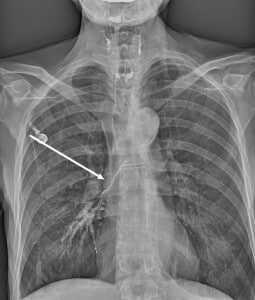

- Обязательным является проведение рентгенографии и рентгеноскопии пищевода с водорастворимым контрастным веществом (барий использовать не рекомендуется, рисунок 1, 2).

Рисунок 1. Пищеводно-респираторный свищ при рентгенографии/рентгеноскопии пищевода